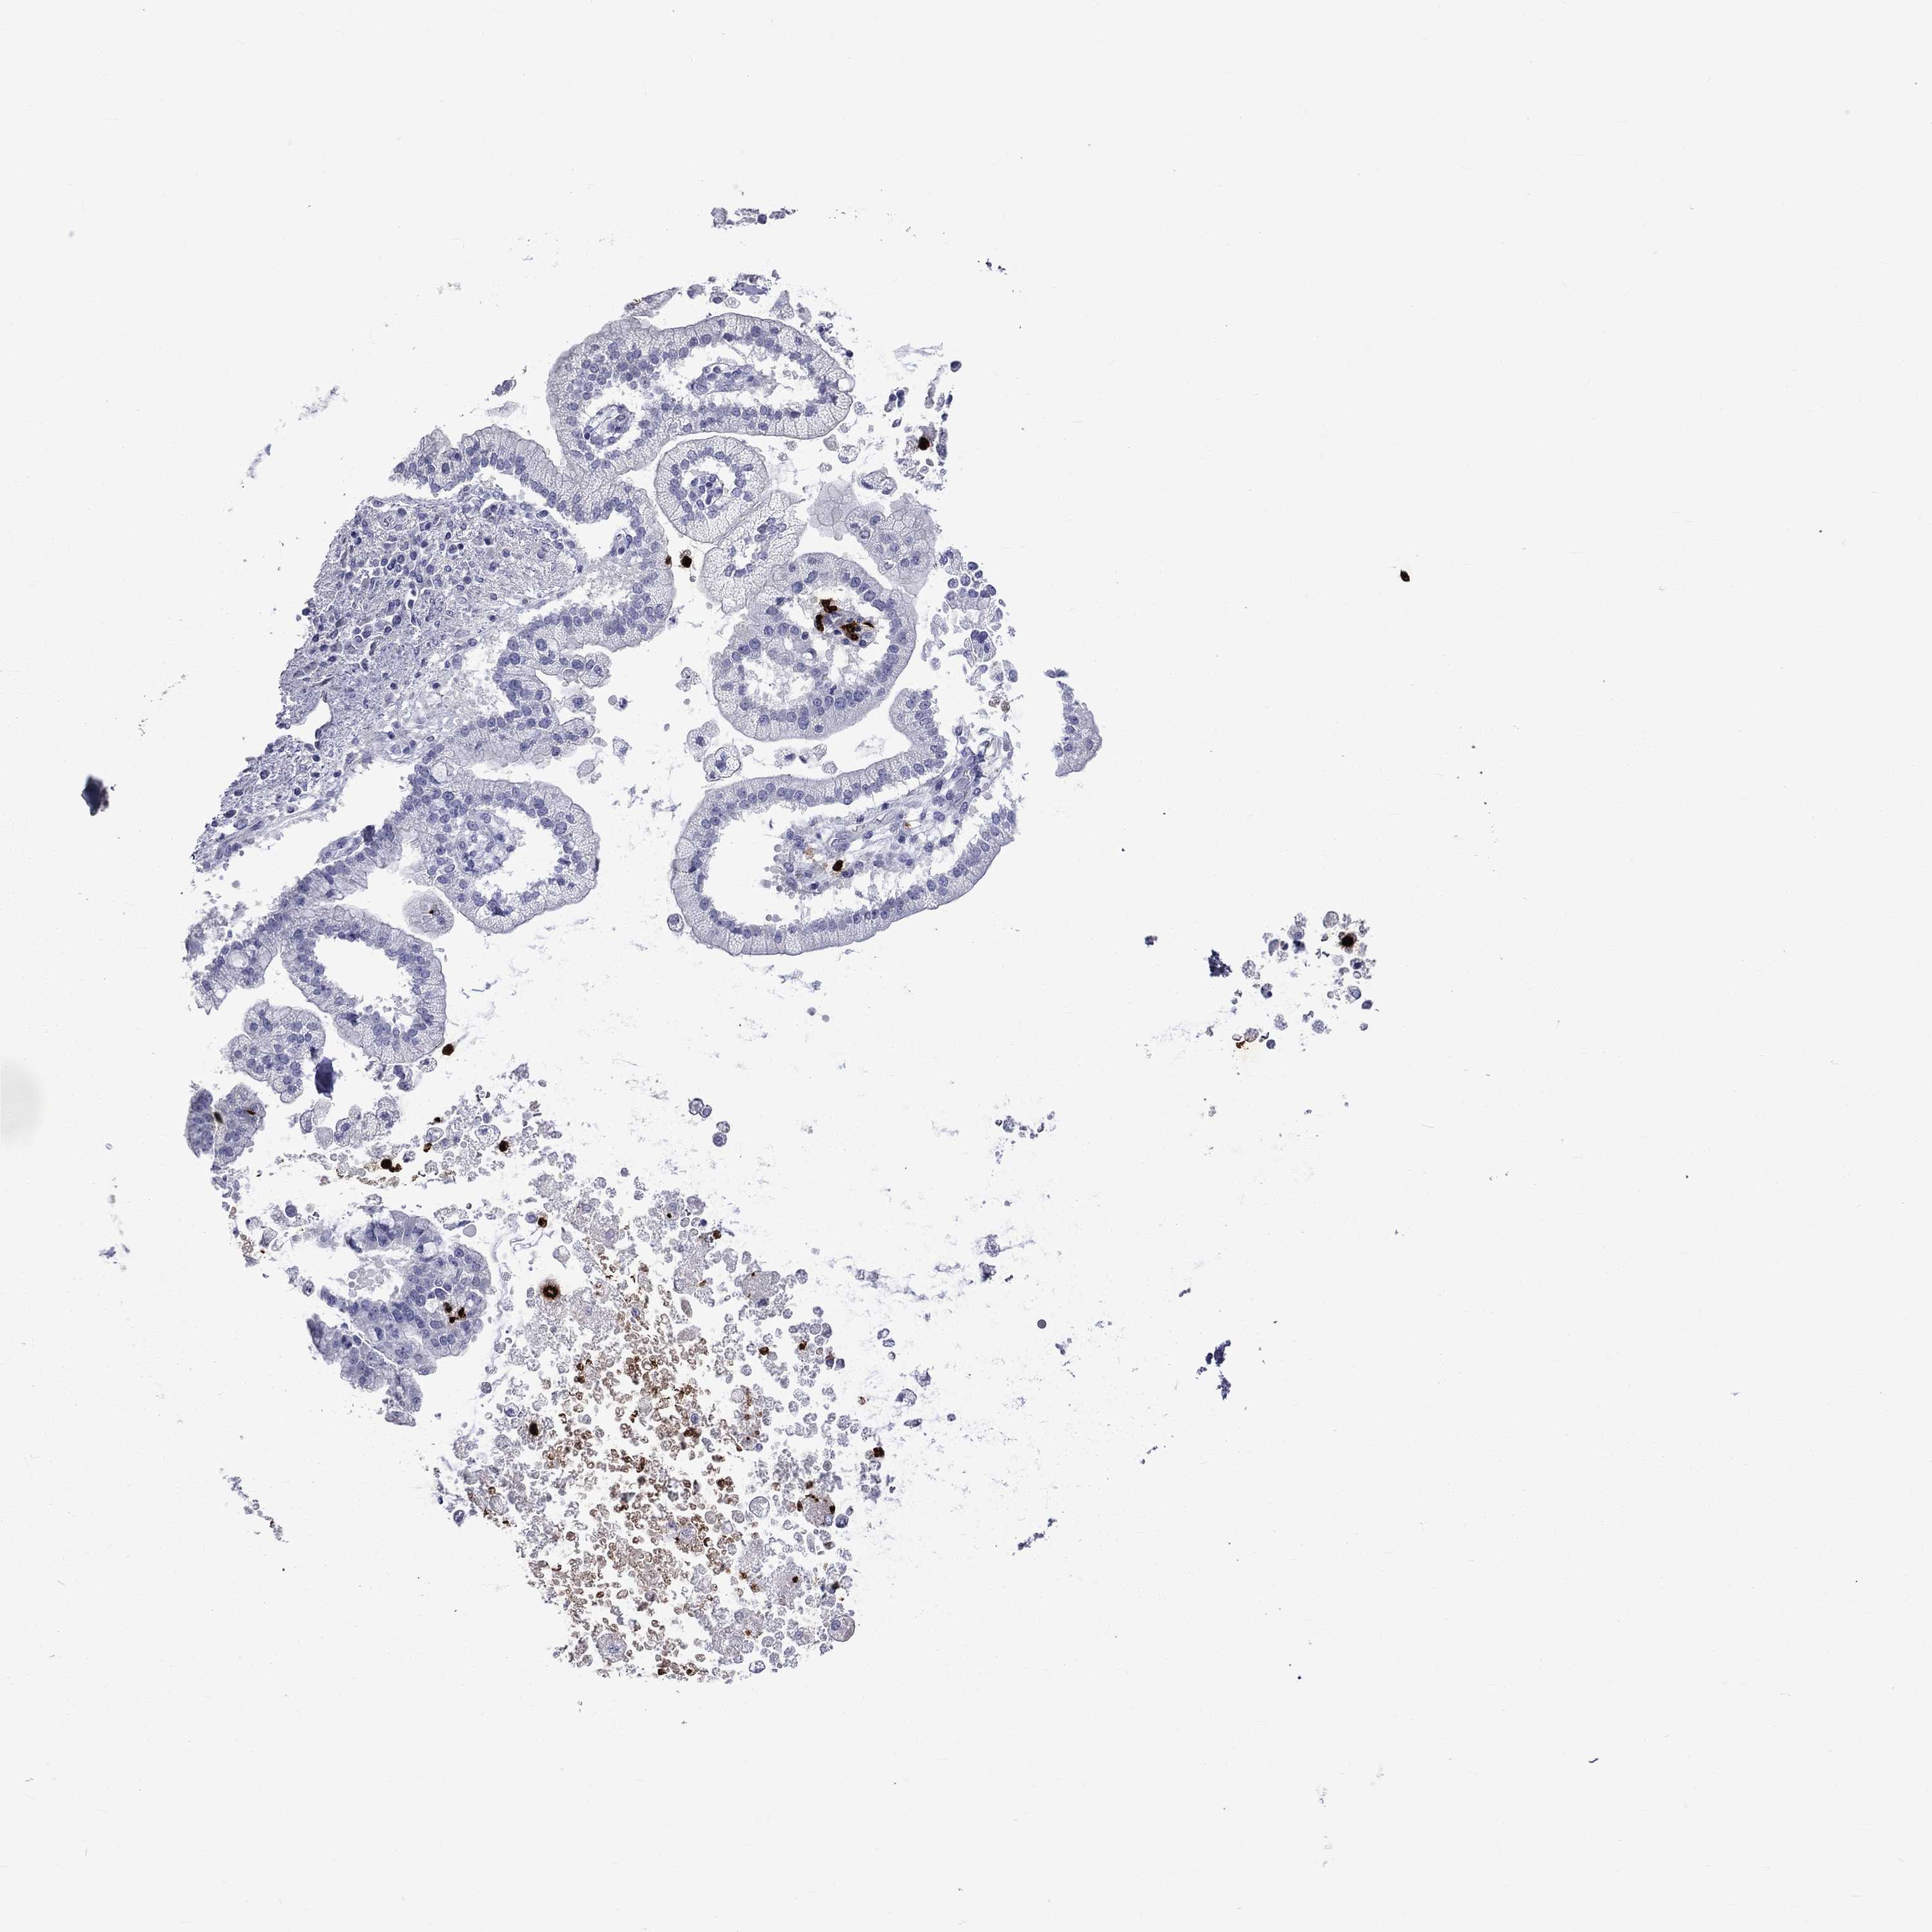

LIVER CANCER - Protein expressioni

A mouse-over function shows sample information and annotation data. Click on an image to view it in a full screen mode. Samples can be filtered based on level of antibody staining by selecting one or several of the following categories: high, medium, low and not detected. The assay and annotation is described here.

Note that samples used for immunohistochemistry by the Human Protein Atlas do not correspond to samples in the TCGA dataset.

Antibody stainingi

Antibody staining in the annotated cell types in the current human tissue is reported as not detected, low, medium, or high, based on conventional immunohistochemistry profiling in selected tissues. This score is based on the combination of the staining intensity and fraction of stained cells.

Each image is clickable and will lead to virtual microscopy that enables deeper exploration of all samples and also displays staining intensity scores, fraction scores and subcellular localization as well as patient and tissue information for each sample.

Antibody HPA066836

Antibody HPA073774

Antibody CAB015409

Staining

High

Medium

Low

Not detected

Carcinoma, Hepatocellular, NOS

Cholangiocarcinoma